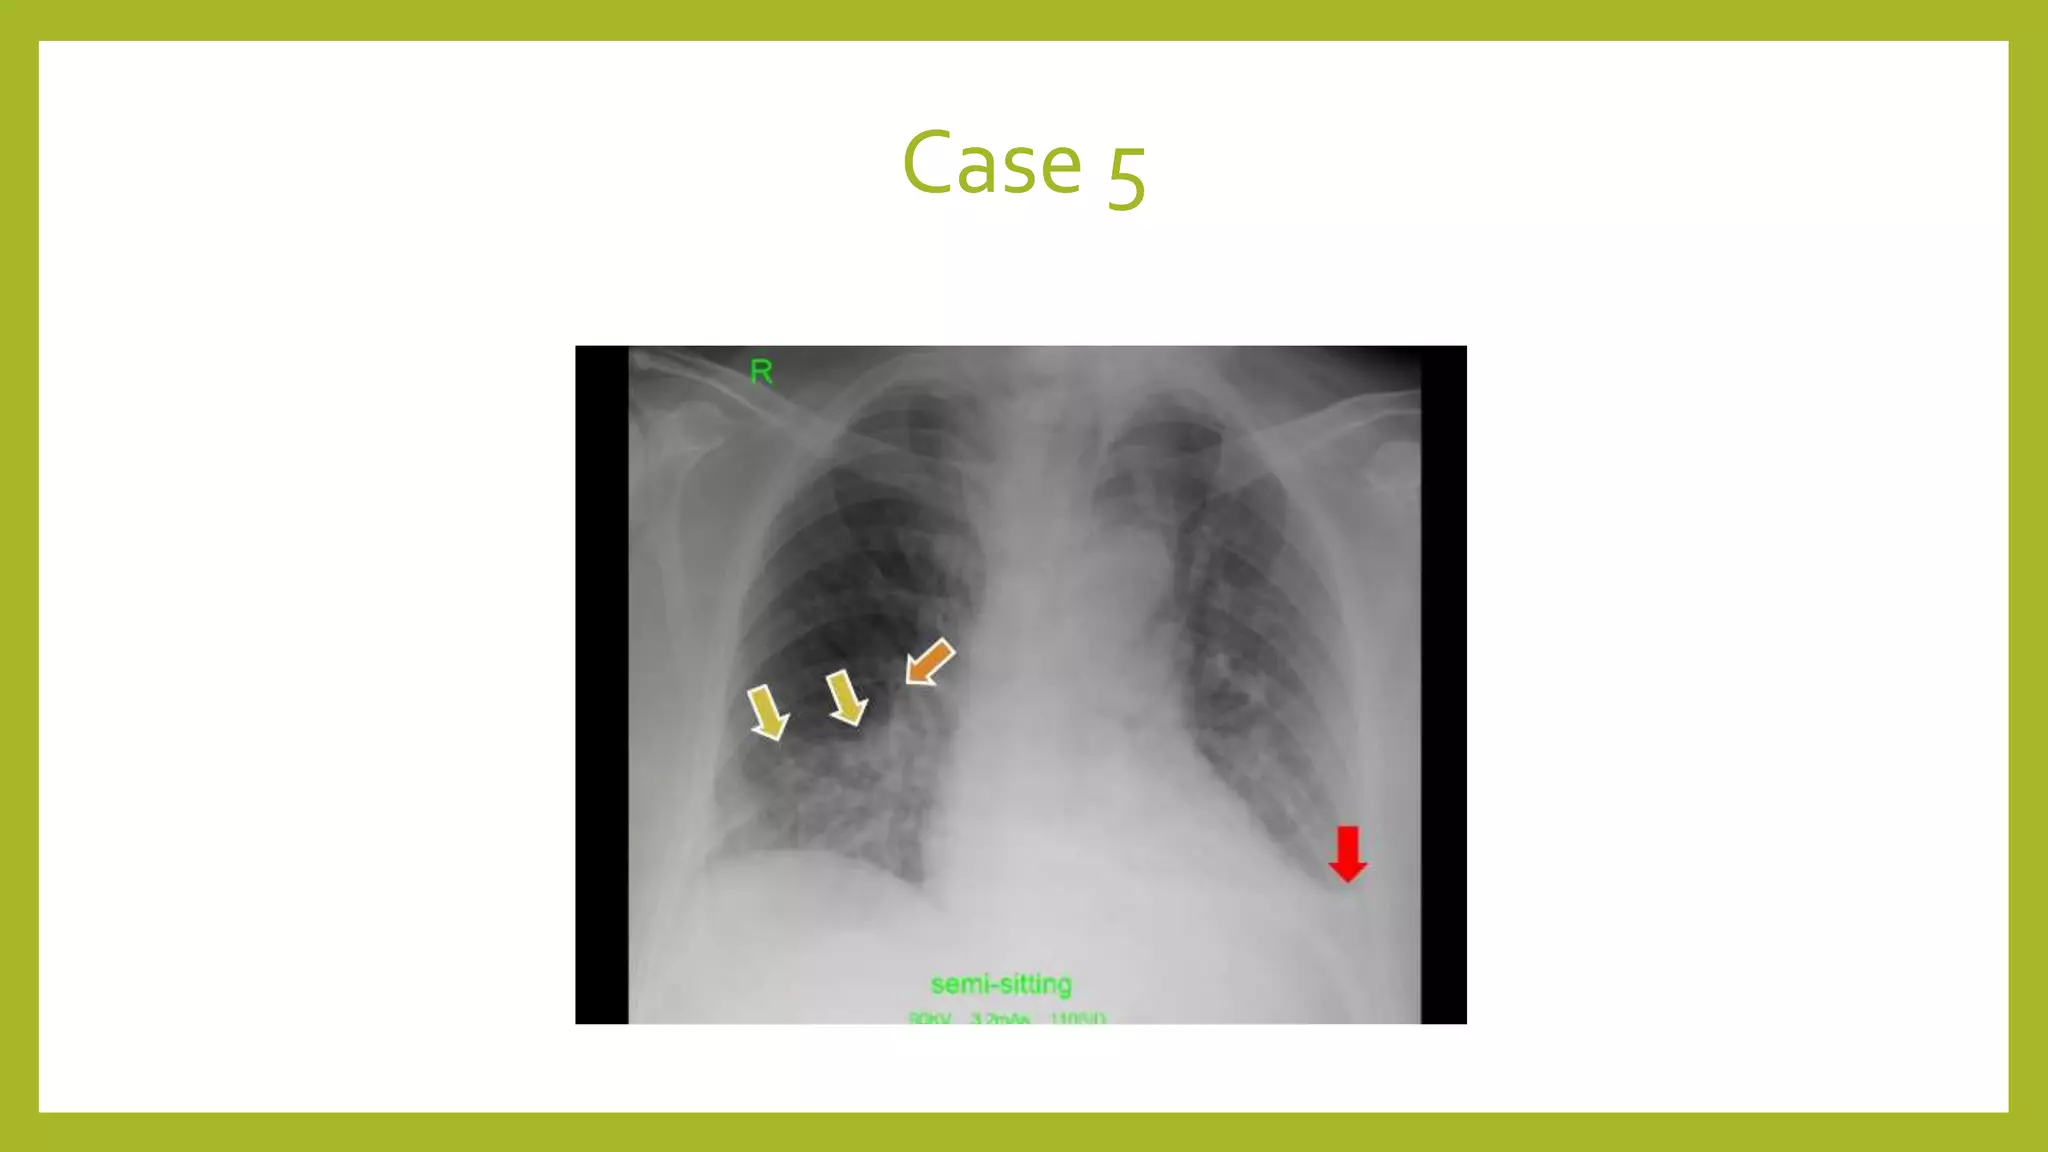

The document provides guidance on approaching and interpreting chest x-rays (CXR). It outlines steps to check the name, date and quality of the film, systematically scan the CXR looking for abnormalities, and determine if the lungs appear too white or black. Specific signs are described to help localize abnormalities, including the cardiac silhouette sign and pleural effusion signs. Examples are given of respiratory distress syndrome, tetralogy of fallot, transposition of great arteries, and total anomalous pulmonary venous return. The take home message is to summarize positive findings, compare to prior CXRs if available, and confirm findings with a radiologist.